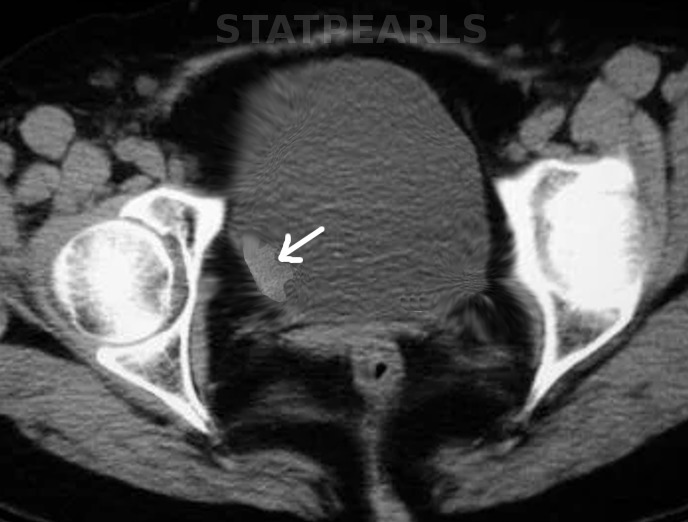

Poorly differentiated urothelial carcinoma, with metaplastic squamous appearance

圖3: 分化差的尿路上皮癌,具有化生性鱗狀外觀。10x,H/E。醫(yī)學(xué)博士 Fabiola Farci 供稿